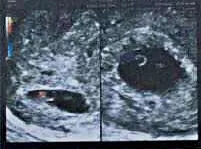

今年中秋节前,35岁的张女士在江湾生殖与遗传医院查血βHCG显示怀孕了。而B超检查更加让她“喜上加喜”——双胎妊娠,并均已见胎心胎芽。

B超提示:宫内早孕,双胎妊娠⏫